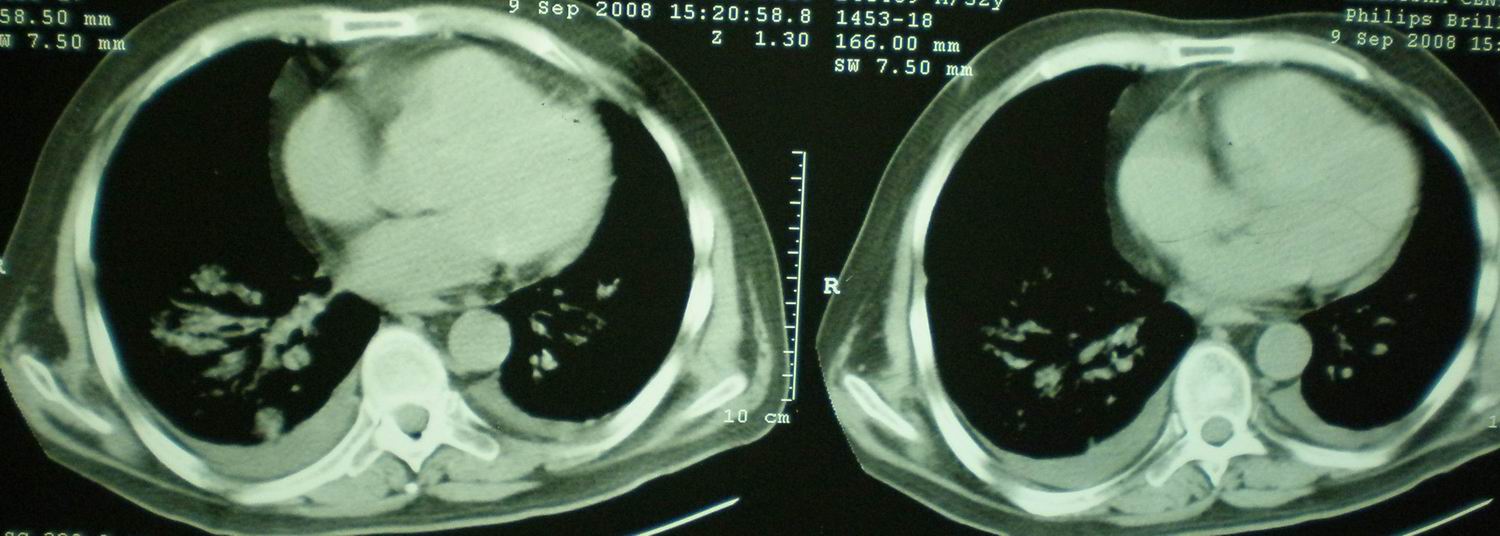

2008年9月18日ct片